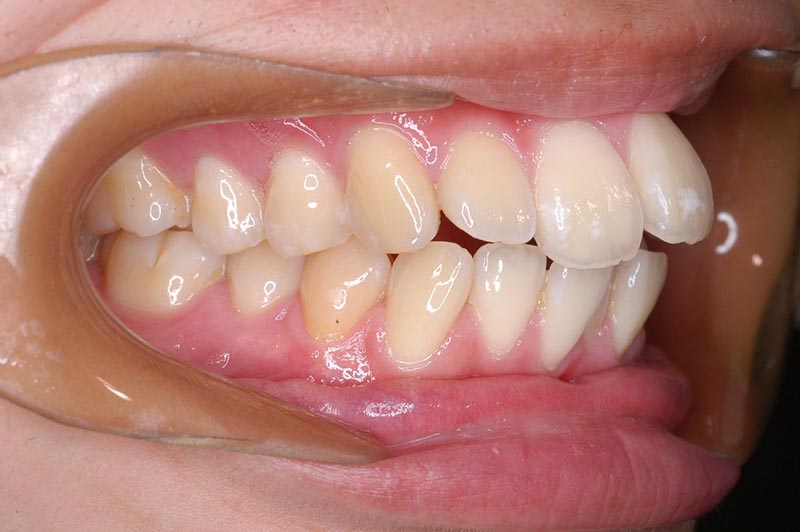

動的治療終了時

FP・IOP

批評・予后 上顎大臼歯のアンカーロスも生じず、大幅な前歯舌側移動、咬合の緊密化、歯根のパラレリングは行えた。上下口唇形態は改善し、良好なプロファイルが得られた。